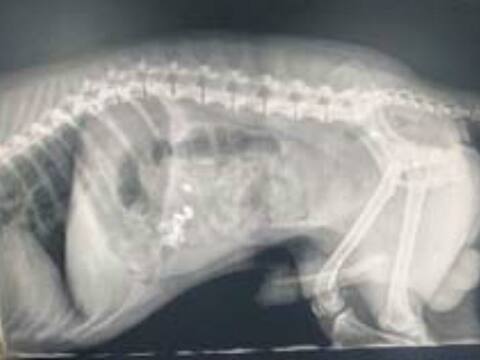

ਹੀਰੇ ਦੀਆਂ ਵਾਲੀਆਂ ਗੁਆਚਣ 'ਤੇ ਉੱਡੇ ਹੋਸ਼, ਸ਼ੱਕ ਪੈਣ 'ਤੇ ਕੁੱਤੇ ਦਾ ਕਰਾਇਆ ਐਕਸਰੇ, ਅੰਤੜੀਆਂ 'ਚ ਫਸੀਆਂ

ਜਲੰਧਰ: ਸਥਾਨਕ ਗੁਰੂ ਰਾਮਦਾਸ ਕਲੋਨੀ ਵਿੱਚ ਰਹਿਣ ਵਾਲੇ ਪਰਿਵਾਰ ਦੇ ਪਾਲਤੂ ਕੁੱਤੇ ਨੇ ਬੈਡਰੂਮ ਵਿੱਚ ਰੱਖੇ ਹੀਰੇ ਦੀਆਂ ਵਾਲੀਆਂ ਨਿਗਲ ਲਈਆਂ। ਵਾਲੀਆਂ ਗਾਇਬ ਹੋਣ ’ਤੇ ਪਹਿਲਾਂ ਪਰਿਵਾਰ ਨੇ ਬਥੇਰੀ ਤਲਾਸ਼ ਕੀਤੀ ਪਰ ਕਿਤੇ ਵੀ ਕੋਈ ਸੁਰਾਗ ਨਹੀਂ ਮਿਲਿਆ। ਘਰ ਵਿੱਚ ਕੁੱਤੇ ਤੋਂ ਇਲਾਵਾ ਕੋਈ ਹੋਰ ਮੌਜੂਦ ਨਹੀਂ ਸੀ। ਇਸ ਲਈ ਘਰ ਵਾਲਿਆਂ ਨੂੰ ਸ਼ੱਕ ਹੋਇਆ ਕਿ ਕਿਤੇ ਕੁੱਤੇ ਨੇ ਹੀ ਨਾ ਹੀਰੇ ਦੀਆਂ ਵਾਲੀਆਂ ਨਿਗਲ ਲਈਆਂ ਹੋਣ। ਇਸ ਪਿੱਛੋਂ ਸ਼ੱਕ ਦੇ ਆਧਾਰ ’ਤੇ ਪਰਿਵਾਰ ਕੁੱਤੇ ਨੂੰ ਲੈ ਕੇ ਪਸ਼ੂਆਂ ਦੇ ਡਾਕਟਰ ਕੋਲ ਪੁੱਜੇ ਜਿੱਥੇ ਡਾਕਟਰ ਨੇ ਕੁੱਤੇ ਦਾ ਐਕਸਰੇਅ ਕਰਵਾਉਣ ਲਈ ਕਿਹਾ। ਕੁੱਤੇ ਨੂੰ ਉਲਟੀ ਦੀ ਦਵਾਈ ਵੀ ਦਿੱਤੀ ਗਈ ਪਰ ਕੁਝ ਨਹੀਂ ਹੋਇਆ। ਡਾਕਟਰ ਮੁਕੇਸ਼ ਗੁਪਤਾ ਨੇ ਕਿਹਾ ਕਿ ਕੁੱਤੇ ਦੇ ਐਕਸਰੇਅ ਤੋਂ ਸਪਸ਼ਟ ਹੋ ਗਿਆ ਹੈ ਕਿ ਵਾਲੀਆਂ ਉਸ ਦੇ ਢਿੱਡ ਤੇ ਅੰਤੜੀਆਂ ਵਿੱਚ ਫਸੀਆਂ ਹੋਈਆਂ ਹਨ। ਹਾਲਾਂਕਿ ਕੁੱਤੇ ਨੂੰ ਕੋਈ ਤਕਲੀਫ ਨਹੀਂ ਹੋ ਰਹੀ। ਇਸ ਸਬੰਧੀ ਡਾਕਟਰ ਜੀਐਸ ਬੇਦੀ ਨੇ ਦੱਸਿਆ ਕਿ ਪਾਲਤੂ ਕੁੱਤੇ ਖਿਡੌਣੇ, ਸੋਨੇ ਦੀਆਂ ਵਾਲੀਆਂ, ਅੰਗੂਠੀ ਜਾਂ ਚੇਨ ਆਦਿ ਨਿਗਲ ਲੈਂਦੇ ਹਨ। ਜੇ ਕੁੱਤੇ ਦੀ ਉਮਰ ਘੱਟ ਹੋਵੇ ਤਾਂ ਆਪ੍ਰੇਸ਼ਨ ਕਰਕੇ ਸਾਮਾਨ ਕੁੱਤੇ ਦੇ ਸਰੀਰ ਵਿੱਚੋਂ ਕੱਢਿਆ ਜਾ ਸਕਦਾ ਹੈ। ਫਿਲਹਾਲ ਕੁੱਤੇ ਦੀ ਉਮਰ ਜ਼ਿਆਦਾ ਹੈ ਇਸ ਲਈ ਡਾਕਟਰ ਉਸ ਨੂੰ ਉਲਟੀ ਕਰਵਾਉਣ ’ਤੇ ਜ਼ੋਰ ਦੇ ਰਹੇ ਹਨ।